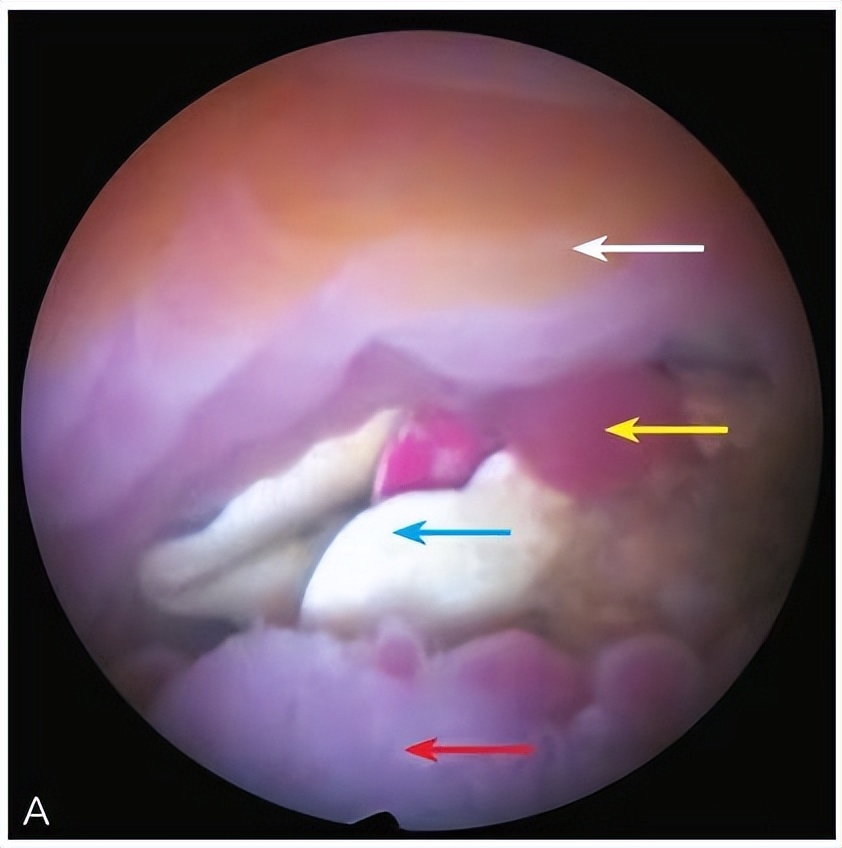

1)宫腔残留、宫内节育器异位或嵌顿、宫腔及阴道内异物的定位和取出;

*女幼**阴道异物